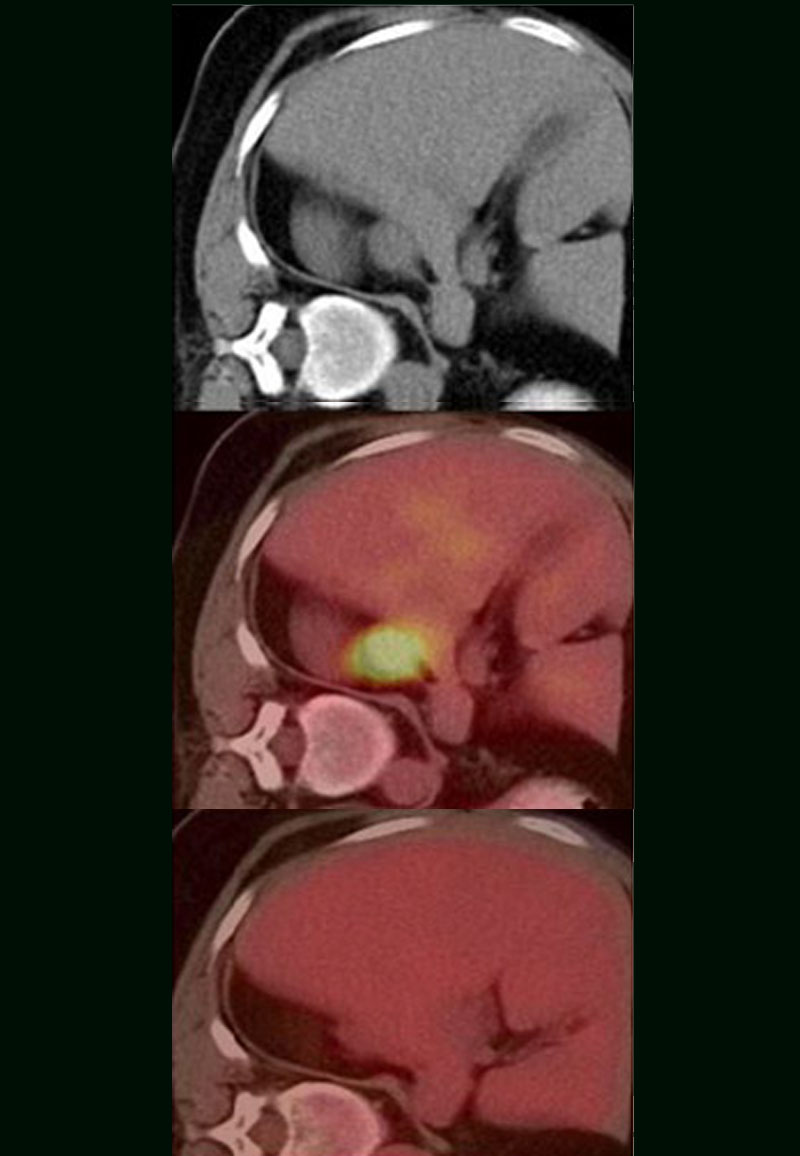

Finalmente, el resultado de estos estudios carecería de valor si no se realizan estudios clínicos que puedan escalarlo o extrapolarlo al tratamiento en seres humanos. Para tal objetivo, el equipo de investigación de Barbault fue el primero en ocupar la terapia PEMF en el tratamiento de cáncer en humanos [14]. Los investigadores utilizaron un rango de frecuencias desde los 0.1 Hz hasta los 114 kHz para tratar a 163 pacientes con diferentes tipos de cáncer, entre los que se incluían cerebrales, colorrectales, carcinomas, pancreático, de mama, de próstata, de pulmón y de ovario. Los pacientes se administraron la terapia PEMF por 60 Newsletter informativo Vol. IV, Noviembre, 2019 minutos, tres veces al día, por un promedio de 278.4 meses. A lo largo del tratamiento, a la terapia de estimulación magnética no mostró efectos adversos en los pacientes e incluso en algunos casos brindo estabilidad de hasta 6 meses en la enfermedad. Los investigadores detectaron por medio de un sistema de detección de frecuencias, especificidad de frecuencias para cada tipo de tumor. Más importante aún en algunos casos lograron observar disminución en los tumores (figura 4). Estos resultados resultan prometedores para el diseño de terapias personalizadas para los pacientes para favorecer la supervivencia del paciente y la disminución de los tumores a largo plazo

Figura 4. Efecto de la estimulación magnética en un caso de cáncer de mama.

A la izquierda se observa el estatus inicial del paciente previo a la terapia, donde se visualiza el tumor. La figura del centro resalta el tumor. La figura de la derecha muestra la desaparición del tumor después del tratamiento con la terapia de estimulación magnética.